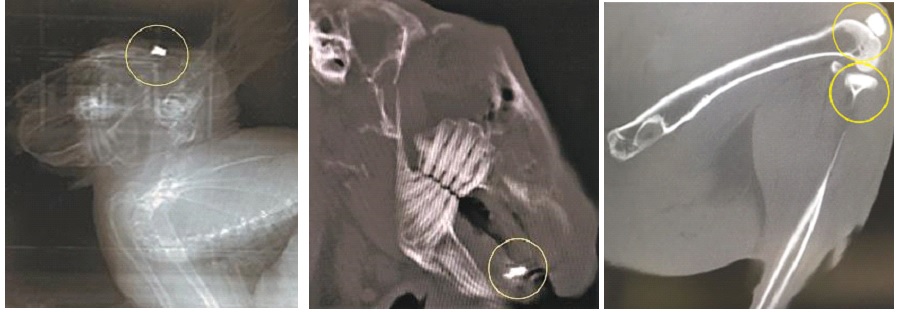

Созданы имплантаты, подобные натуральной кости

Ученые нашли способ создания биоматериалов из синтетических порошков и керамики на основе силиката кальция и его биологически активных композитов. Полученные из них имплантаты по структуре и свойствам подобны натуральной кости и могут стимулировать ее рост в организме человека. Статья об этом опубликована в журнале Progress in Natural Science: Materials International. Исследования поддержаны грантом Президентской программы исследовательских проектов Российского научного фонда.

Биоматериалы работают в непосредственном контакте с живыми тканями и клетками внутри организма. Наиболее крупные области их применения – производство медицинских имплантатов, в том числе костных. В качестве исходного сырья используются распространенные дешевые и доступные природные материалы, а технологии позволяют делать их биоактивными. Попадая в организм, такие системы взаимодействуют с костной тканью: стимулируют рост, способствуют миграции, делению и дифференцировке клеток.

К таким материалам существуют свои требования. Во-первых, они не должны оказывать отрицательного влияния на живые системы. Это главное условие, которое определяется химическим составом, свойствами поверхности и физическими показателями компонентов материала. Во-вторых, у искусственной кости должна была пористая структура. Только тогда клетки костной ткани и кровеносные сосуды прорастают внутрь имплантата. В-третьих, необходимо, чтобы материал обладал биологически активными свойствами, мог влиять на физиологические процессы в организме. Также его компоненты не должны конкурировать между собой в реакциях внутри клеток и препятствовать росту костей. Например, в одном биоматериале невозможно совмещать кальций и конкурирующий с ним алюминий. Ранее было доказано, что биологически активный порошок силиката кальция положительно влияет на метаболизм.

Преимущество созданных синтетических материалов в том, что при производстве им можно задавать нужные характеристики и свойства. Авторы новой статьи нашли способ, который делает керамику и порошок силиката кальция активными при введении их в организм, но при этом сохранится необходимая для имплантатов структура и прочность. Для синтеза порошка использовали золь-гель технологию. Это хорошо изученный и достаточно популярный в мире метод: исходный раствор становится порошком из наночастиц. При работе с керамикой исследователи применяли оригинальную технологию искрового плазменного спекания – синтеза керамики из полученных ранее порошков силиката кальция с разными биологически активными добавками. Эта технология еще мало изучена в мире.

Преимущество таких изделий – в сочетании полного набора совместимых с организмом свойств самих материалов и доступных методов их синтеза. А добавки наночастиц благородных металлов – золота и серебра – придают имплантатам антибактериальные и противовоспалительные свойства.

Полученные из этих материалов протезы можно считать высококачественным продуктом. Исключительная биологическая совместимость позволяет протезировать пациентов любого возраста. Также для костной хирургии это относительно дешевые и доступные биоматериалы из отечественного сырья. В будущем имплантаты могут поступить в промышленное производство, и наоборот, будут востребованы в области персонализированной медицины.